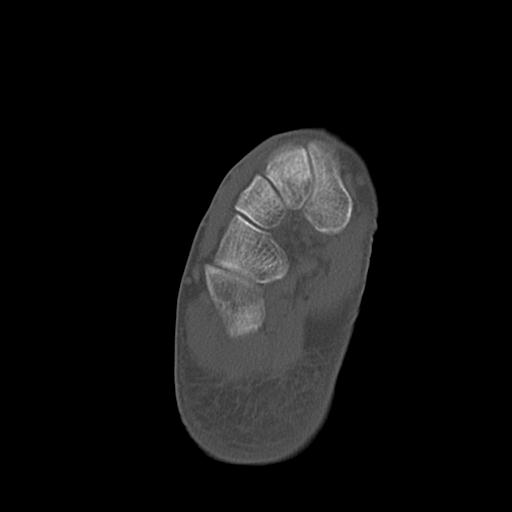

102803 1/12(キウスなし) 1/27 左下腿 4R 30歳女性 左脛骨軸内釘